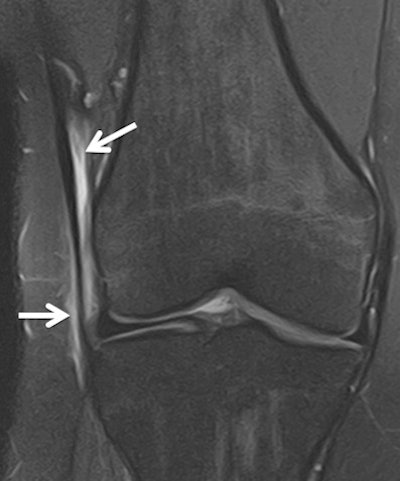

However, in the run to the games they have seen several typical sports injuries, including a fatigue stress fracture in the heel of a long distance runner and a case of iliotibial band syndrome in the knee of a hockey player (see images).

Female hockey player, 18, with anterolateral knee pain for two days. Coronal T2-weighted fat-saturated image (Toshiba, Elan 1.5-tesla) shows high-signal intensity around the iliotibial band on the lateral aspect of the knee in keeping with iliotibial band syndrome. This is thought to be caused by friction of the band as it repeatedly crosses the lateral condyle during flexion and extension.Reflecting on the robust mentality of the elite athlete, Ritchie related the story of one judo competitor who dislocated her elbow six years previously but who has overcome this injury and competed at a very high level. She then presented with an acute, chronic injury. MRI showed fragments of bone avulsed from both epicondyles, scarred medial and lateral collateral ligaments, as well as partial tears of the common flexor and extensor tendons, joint effusions, and intra-articular bodies. There was a lot of post-traumatic change in the elbow, but she is still performing.